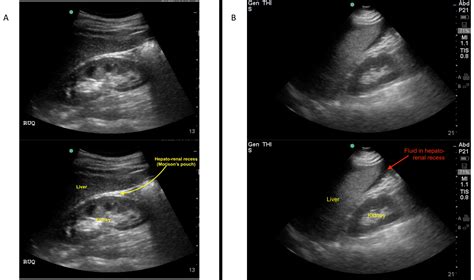

• EFAST (Extended Focused Assessment with Sonography for Trauma): This is a comprehensive ultrasound examination used to evaluate patients with trauma. It includes views of the heart, lungs, abdomen, and pelvis to detect fluid collections, pneumothorax, and other injuries.

• Trauma Assessment: In trauma patients, the Fast Exam Ultrasound helps identify internal injuries, such as hemoperitoneum, hemothorax, and pericardial effusion.

• Anatomical Landmarks: Identify key anatomical landmarks to accurately interpret the images.

• Pathological Findings: Look for signs of pathology, such as fluid collections, organ abnormalities, and other conditions.